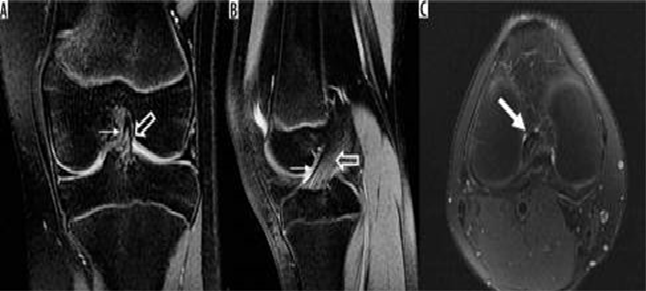

Hình 4. Rách sụn chêm, nang sụn chêm. Hình ảnh coronal xóa mỡ có u nang nhỏ (mũi tên đen) tiếp giáp với thân của sụn chêm bên có vết rách liên quan đến sụn chêm (mũi tên trắng)

Hình 5. Vết rách ngang sụn với mảnh di lệch. Hình ảnh pd xóa mỡ với vết rách sụn chêm giữa và mảnh di lệch (mũi tên) nằm giữa dây chằng chéo giữa và mâm chày giữa.

Hình 7. Vết rách ngang sụn. Hình ảnh pd coronal xóa mỡ với tín hiệu tuyến tính trong sụn (mũi tên đóng) kéo dài đến mặt dưới của thân sụn bên, phù hợp với vết rách. Tín hiệu cao (mũi tên mở) ở mặt ngoài, mặt sụn giữa không kéo dài đến bề mặt tạo hình sụn và phù hợp với thoái hóa niêm mạc.

Hình 8. Nước mắt tay cầm xô lệch. A và B là hình ảnh cộng hưởng từ pd xóa mỡ với vết rách tay cầm cho thấy một mảnh sụn dịch chuyển liền kề với dây chằng chéo sau (mũi tên trắng), được gọi là dấu hiệu "dây chằng chéo sau đôi ", cũng như một mảnh sụn bị dịch chuyển trong rãnh liên chất (mũi tên đen). C là hình ảnh pd xóa mỡ với vết rách ở tay cầm cho thấy mảnh bị dịch chuyển ra phía trước (mũi tên trắng), tiếp giáp với sừng trước, được gọi là dấu hiệu "sừng trước kép".